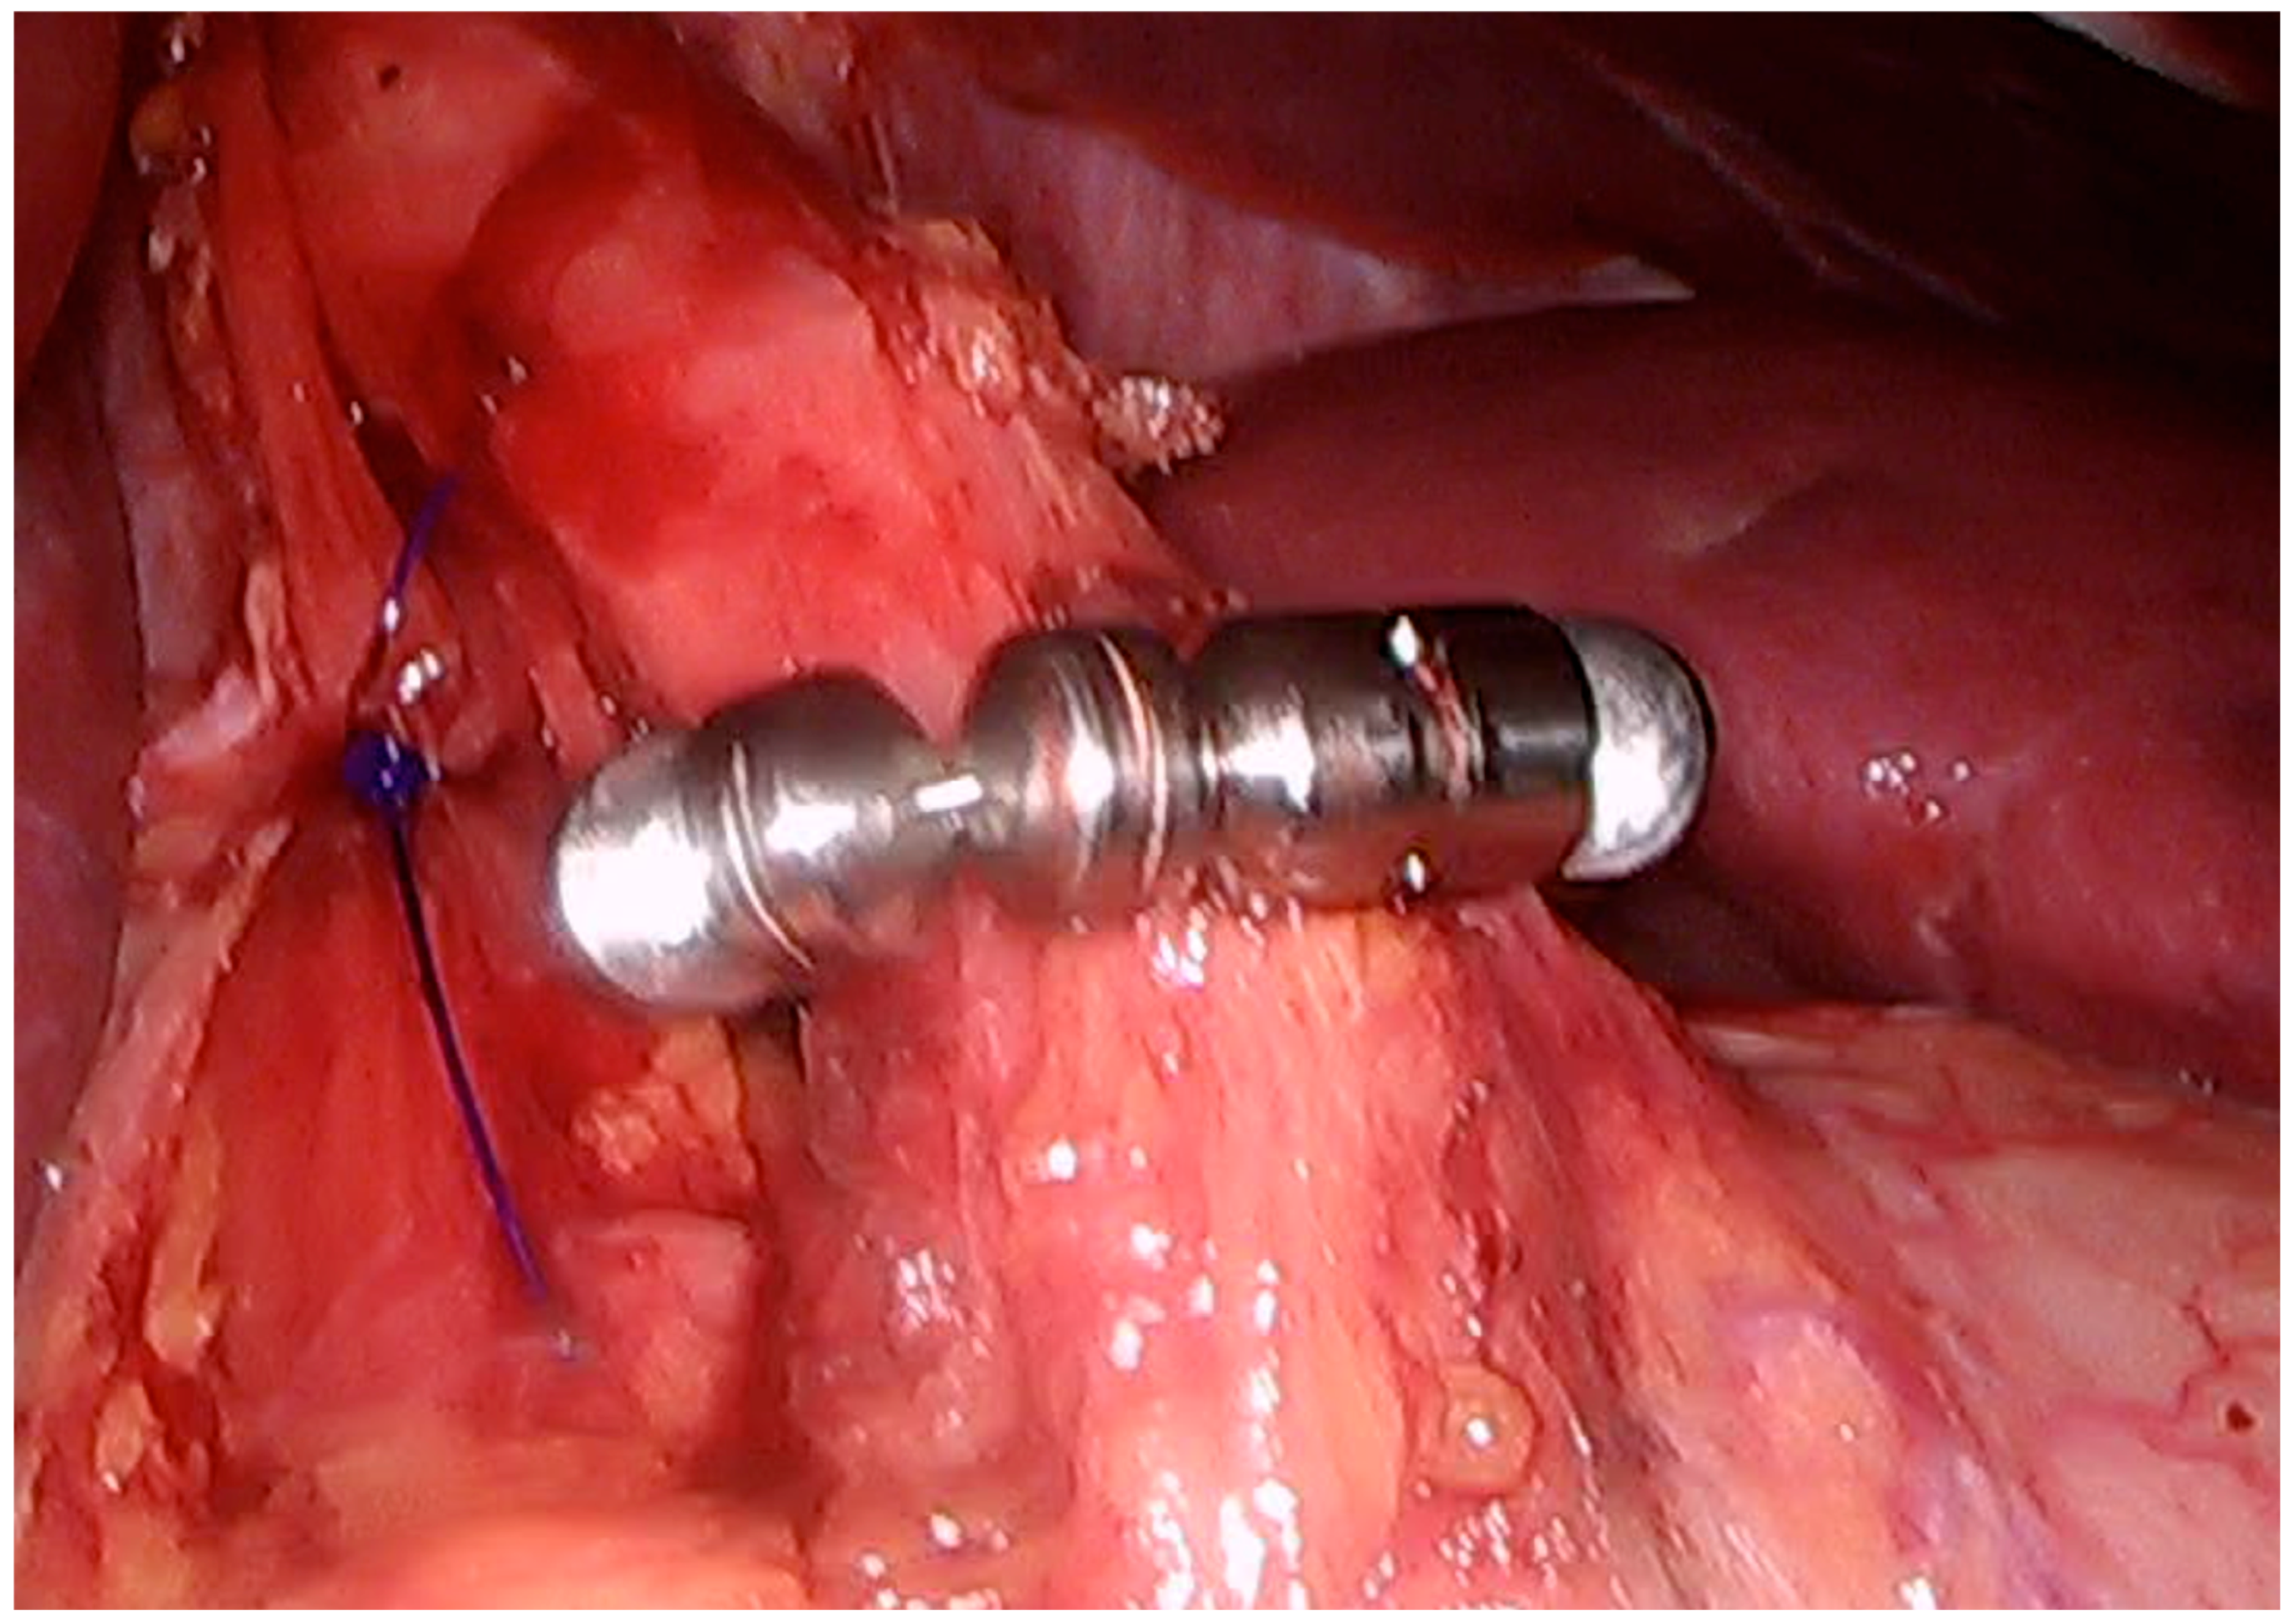

Magnetic Sphincter Augmentation

16. Efficacy in GERD Management

17. Morbidity and Complications

17.1. Dysphagia

17.2. Risk of Erosion and Migration